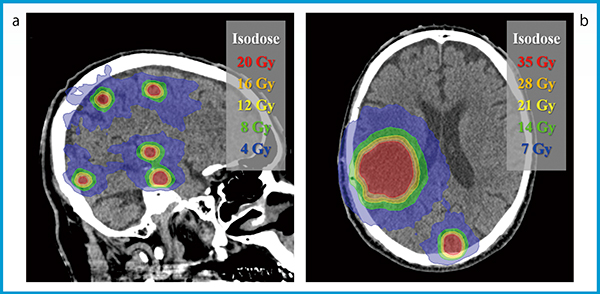

HyperArcの治療計画は,腫瘍の数およびサイズによらず,腫瘍に対する高い線量集中性を示す(図2)。千葉県がんセンターにおいて,SRTの処方線量は,腫瘍径に応じて表1のとおり決定され,肉眼的腫瘍体積(GTV)に全方1mmのマージンを付与した計画標的体積(PTV)の95%以上に投与される(D95%処方)。加えて,50%等線量曲線は,SRS-NTOを用いて最適化計算することで,PTV表面から5mm以内に収まるように調整される。SRS-NTOのみでは低線量域の制御が困難となる場合,ターゲット周囲にリング状の輪郭を作成し,最適化計算に利用することで線量分布形状の改善を図る7)。HyperArcの導入以降,SRTの治療計画に要する時間は従来よりも短縮したため,患者治療はシミュレーションCT撮影から最短で2日後に開始される。

図2 HyperArcを用いて計画された定位放射線治療の線量分布

a:10個の微小な腫瘍に対する治療計画(20Gy/単回)

b:直径15mm(35Gy/5分割)および45mm(30Gy/5分割)の腫瘍に対する治療計画